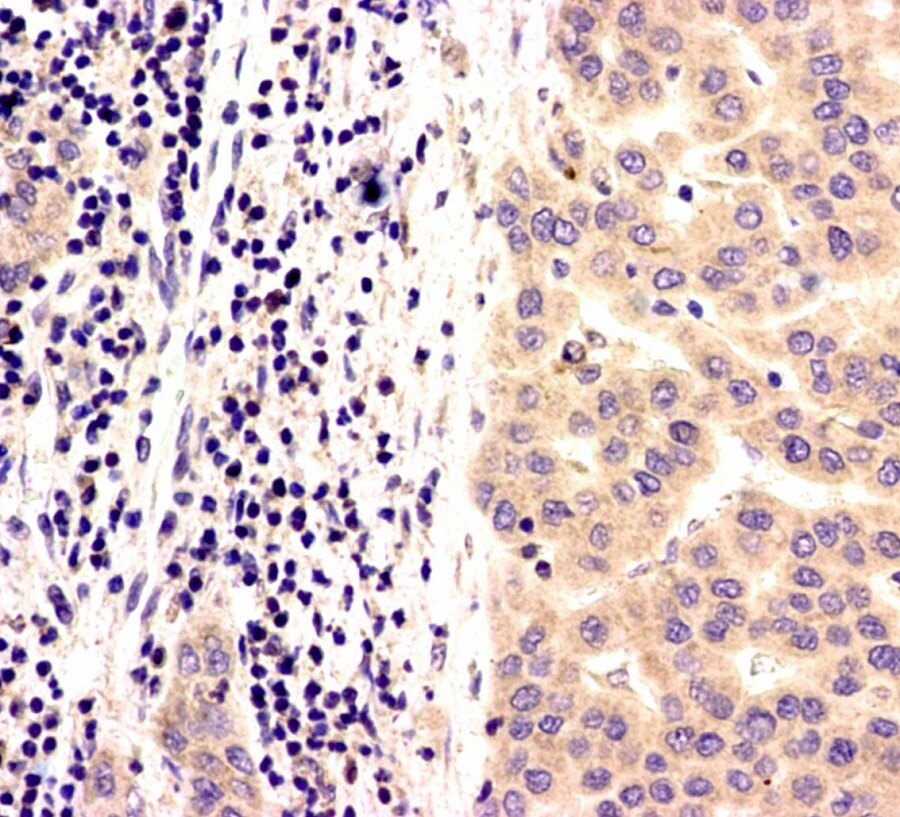

免疫组化,即免疫组织化学检测,是病理诊断中一种常用的检测手段。即对送检的标本进行切片、染色,进而根据化学反应使标记抗体的特殊显色剂显色,以此来确定组织细胞内的抗原,对其进行定位、定性及定量的研究。我们通过这些能看到的结果再做出合理的判断,提供给临床医师,为临床治疗医师提供治疗依据。

一般来说,对于常见的肿瘤类型诊断,依据病变形态就能做出明确病理诊断,不需要做免疫组化检查的。但是,临床碰到的有些肿瘤类型少见,或相似,就需要借助免疫组化检查进一步排除相似的病变。也就是,我们要通过免疫组化检查,才能进一步确定肿瘤亚型,这样临床才能精准治疗。